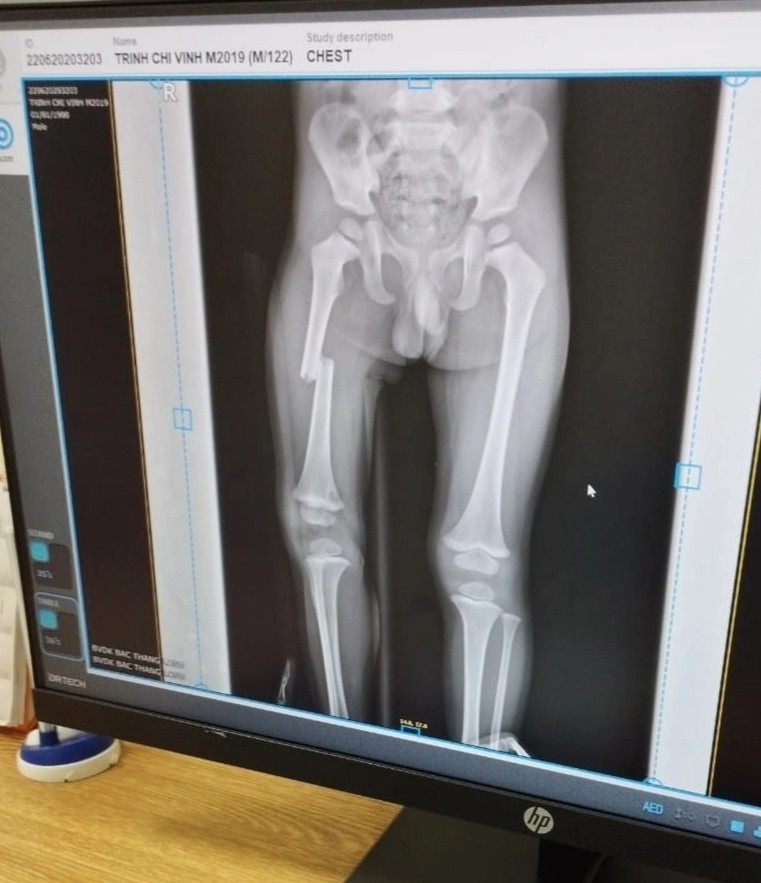

Ảnh chụp X-quang xương chân cháu bé. Ảnh: Gia đình cung cấp.